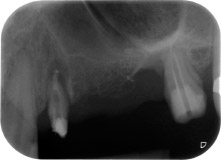

apical periodontal lesion at tooth 24

Fig. 1: 58-year-old patient. Preoperative radiograph showing an apical periodontal lesion at tooth 24 and horizontal loss of alveolar bone in the second quadrant.

A 58-year-old female patient complained of pain and increased mobility of her bridge abutment tooth 24. Periodontal inflammation was present with pocket depths of 7 mm mesiobuccally and more than 12 mm distally, as well as third-degree furcation involvement. Moreover, the radiograph revealed an extensive periodontal lesion around the apical region of the (alio loco) endodontically pretreated tooth 24 (Fig. 1).

One year earlier, teeth 25 and 26 had been extracted due to trauma and for endo-perio reasons, prior to the placement of the bridge. A combined endo-perio lesion was diagnosed for tooth 24, of unclear aetiology. The patient wanted to keep her bridge abutment teeth 24 and 27 and would not accept a final, or even temporary, removable prosthesis. Therefore, it was agreed to make all efforts to retain both teeth, in spite of their poor prognosis as based on radiological and clinical findings.